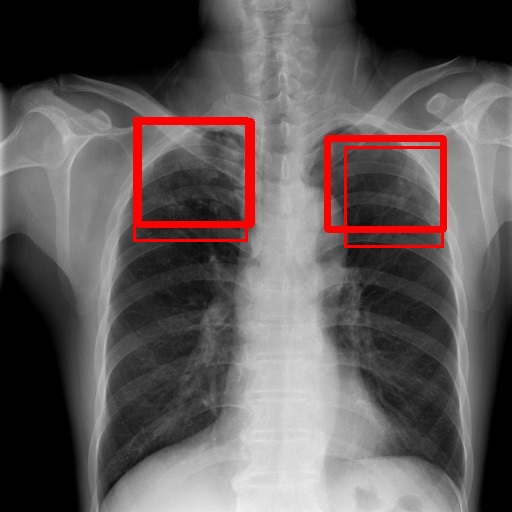

To achieve our goal, our TBX11K dataset includes bounding box annotations for TB infection areas in CXR images. To the best of our knowledge, this is the first dataset designed for TB infection area detection. These annotations are carried out by experienced radiologists from top hospitals. Specifically, each TB CXR image in the dataset is first labeled by a radiologist with 5-10 years of experience in TB diagnosis. Subsequently, another radiologist with over 10 years of experience in TB diagnosis reviews the box annotations. The radiologists do not just label bounding boxes for TB areas but also identify the type of TB (active or latent) for each box. To ensure consistency, the labeled TB types are double-checked against the image-level labels produced by the golden standard. In the event of a mismatch, the CXR image is placed in the unlabeled data for re-annotation, and the annotators do not know which CXR image was previously labeled incorrectly. If a CXR image is labeled incorrectly twice, we inform the annotators of the gold standard for that CXR image and request that they discuss how to re-annotate it. This double-checked process ensures that the annotated bounding boxes are highly reliable for TB infection area detection. Additionally, non-TB CXR images are only labeled with image-level labels produced by the golden standard. Examples of the TBX11K dataset are shown in Fig. 6, and the distribution of TB bounding box sizes is displayed in Fig. 3, indicating that most TB bounding boxes are in the range of .

6.4 Visualization

To gain insights into the learning process of deep neural networks on CXR images, we visualize the feature map of SymFormer w/ RetinaNet at a scale of . To achieve this, we employ principal component analysis (PCA) to reduce the channels of the feature map to a single channel. The resulting single-channel map is then converted into a heat map for visualization purposes. The visualization of the learned features, along with the corresponding detection results, are presented in Fig. 6. Upon analysis, we observe that the visualization of healthy cases exhibits irregular feature patterns, indicating the absence of significant abnormalities. In contrast, the visualization of sick but non-TB cases displayed some discernible highlights, potentially representing the presence of lesions. For TB cases, the highlights in the visualization map align well with the annotated TB infection areas, thereby indicating the effectiveness of the proposed SymFormer in learning deep features for TB area detection. Furthermore, in Fig. 7, we offer qualitative comparisons between the proposed SymFormer and the baseline models for TB infection area detection. As evident, SymFormer consistently delivers superior qualitative detection results.